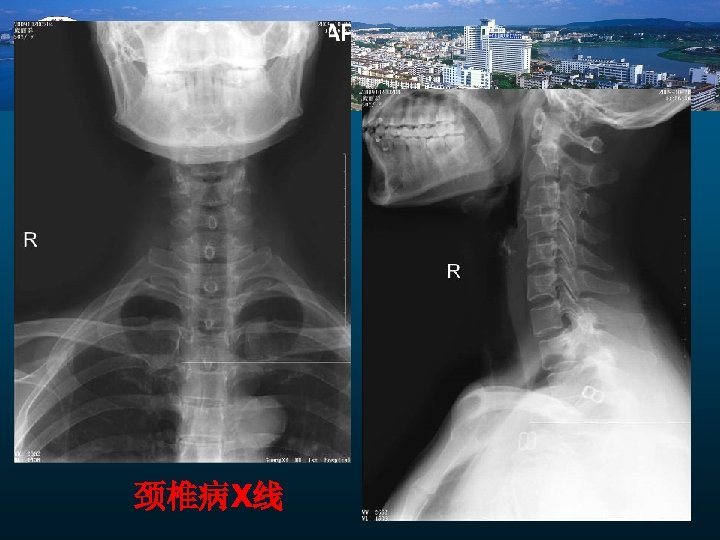

颈椎病X线

小 结 1 、X线及CT可明确显示颈椎病的骨骼改变。 2、 MRI可明确显示椎间盘变性、突出及其附件和脊髓变化, 比较全面对CSM的影像学评价. 但影像学不能轻易诊断颈椎病 3 、 椎管狭窄的MRI测量为了解CSM脊髓压迫提供客观依据 4、 PC-MR脑脊液流速测定为CSM手术效果评价提供依据